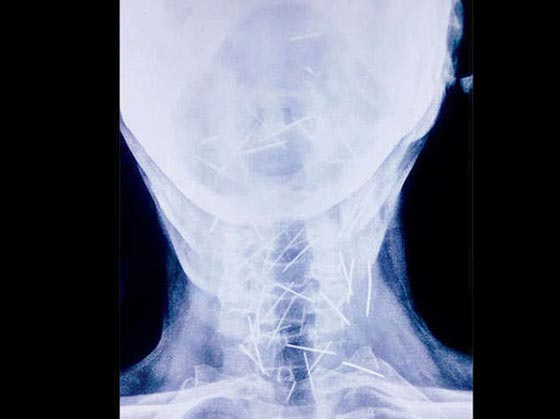

أما آخر حالة حيّرت الأطباء لدى عثورهم على عشرات الدبابيس المغروزة في مختلف أنحاء جسد رجل لا يعرف كيف وصلت هناك! واضطر الهندي بدريلال مينا، البالغ من العمر 56 عاماً، إلى زيارة ستة مستشفيات والخضوع لثلاث عمليات جراحية لاستخراج الدبابيس المغروزة في ذراعيه وقدميه وعنقه. ووفقاً لتقارير الأطباء، أزيل حتى الآن 91 دبوساً، وكان بعضها صدئاً جداً لوجوده هناك لأكثر من ستة أشهر.

ويقول الدكتور لاليت موهان باراشار، الذي أجرى العملية لمينا، "كان إخراجُ الدبابيس بأمان أمراً في غاية الصعوبة، حيث إن بعض الدبابيس كان موجوداً في القصبة الهوائية، والمريء، وحتى في الشريان السباتي الذي يحمل الأكسجين إلى الدماغ". لكن مينا يُصرّ على أنه لم يغرزها بنفسه، ويدعي أنه ليس لديه فكرة عن كيفية دخولها إلى جسده. وكان مينا في بداية الأمر، قد ذهب إلى مستشفى خاص وهو يشكو من آلامٍ في القدم ومن داء السكري؛ ولكن الأطباء وجدوا 75 دبوساً في أجزاء مختلفة من جسده، فيما وجد المعهد الآسيوي للعلوم الطبية في فريداباد (AIMS) - الذي تبنى حالة مينا- 75 دبوساً آخر. ويوضح المعهد أن المهمة الأكثر صعوبة هي "إزالة تلك الدبابيس التي اخترقت الأعصاب الحيوية والشرايين والأعضاء، مثل المريء والشريان السباتي الذي يزود الدم بالدماغ". وأذهل ازدياد عدد الدبابيس الأطباء، لا سيما وأن مينا يُصرُّ هو وأسرتُه على أنه لم يغرز نفسه بهذه الدبابيس، فيما أوصت سلطات المستشفيات بإجراء تقييم نفسي له بعد تعافيه.